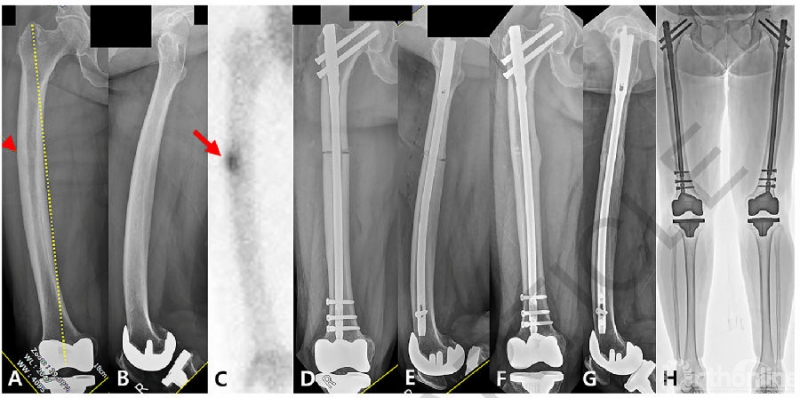

2.长骨干骨折

2.1 胫骨干骨折:基于髓内钉的生物力学优势,已成为胫骨干骨折主要的治疗手段之一,胫骨髓内钉术后生活质量与功能预后、以及切口的方向与术后疼痛的关系等方面仍为研究热点。

社会剥夺是指由于贫穷、歧视或其他边缘化因素而使获得资源的机会有限的状态。Hong Z等[46]调查了社会剥夺和骨科创伤之间的联系,包括患者报告的结局、放射学愈合和胫骨干骨折髓内钉治疗后的并发症发生率。采用区域剥夺指数(ADI)将患者分为最剥夺三分位组(MDT)、中间剥夺三分位组(IDT)和最不剥夺三分位组(LDT)进行结果比较。采用患者报告结局测量信息系统(PROMIS)测量躯体功能(PF)、疼痛干扰(PI)、焦虑和抑郁,采用胫骨骨折影像学愈合量表(RUST)评估骨折愈合情况。结果显示,单因素分析显示,MDT组患者术后1年内PF、PI、焦虑和抑郁评分均较LDT组患者差。在多变量回归分析中,PROMIS评分结局与年龄、种族和吸烟状况有关,而与社会剥夺三分位数无关。此外,与LDT相比,居住在MDT与影像学愈合时间增加31%相关。研究者强调了制定干预措施以减少来自低资源环境的患者面临的不公平的重要性。

Leliveld MS等[47]通过前瞻性多中心随机对照研究,对比分析胫骨髓内钉横行与纵行切口术后膝关节前方1年内疼痛的差异。主要结局指标是基于数字评分量表(NRS)的膝关节跪痛。次要结局指标包括日常活动期间的膝关节疼痛、功能结局(短肌肉骨骼功能评估SMFA和下肢功能量表LEFS)、生活质量(EuroQol-5)、并发症、再次手术和创伤后1年内的费用等。结果显示:术后1年横行切口跪痛评分小于纵行切口,患者对横行切口瘢痕更为满意,横行切口损伤髌下神经的风险降低。生活质量、功能康复、并发症、再手术率、治疗费用两组无明显差别。